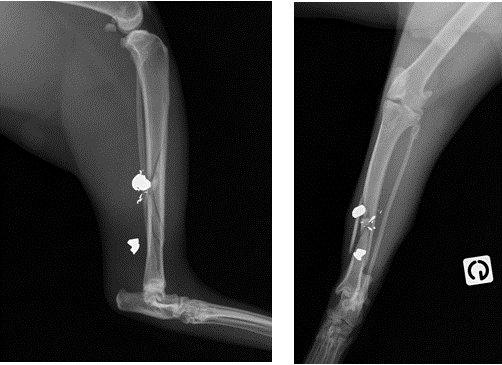

6 semaines post-opératoires, la fracture est stable et le chat ne présente plus de boiterie. Il garde cependant une légère ankylose du tarse physiologique. Les radiographies montrent des implants en place et une cicatrisation osseuse avancée. Un cal déjà minéralisé a ponté certains fragments osseux ; cependant, il reste des zones osseuses non comblées (figure 5).

Figure 5 : Ostéosynthèse 6 semaines post-opératoires